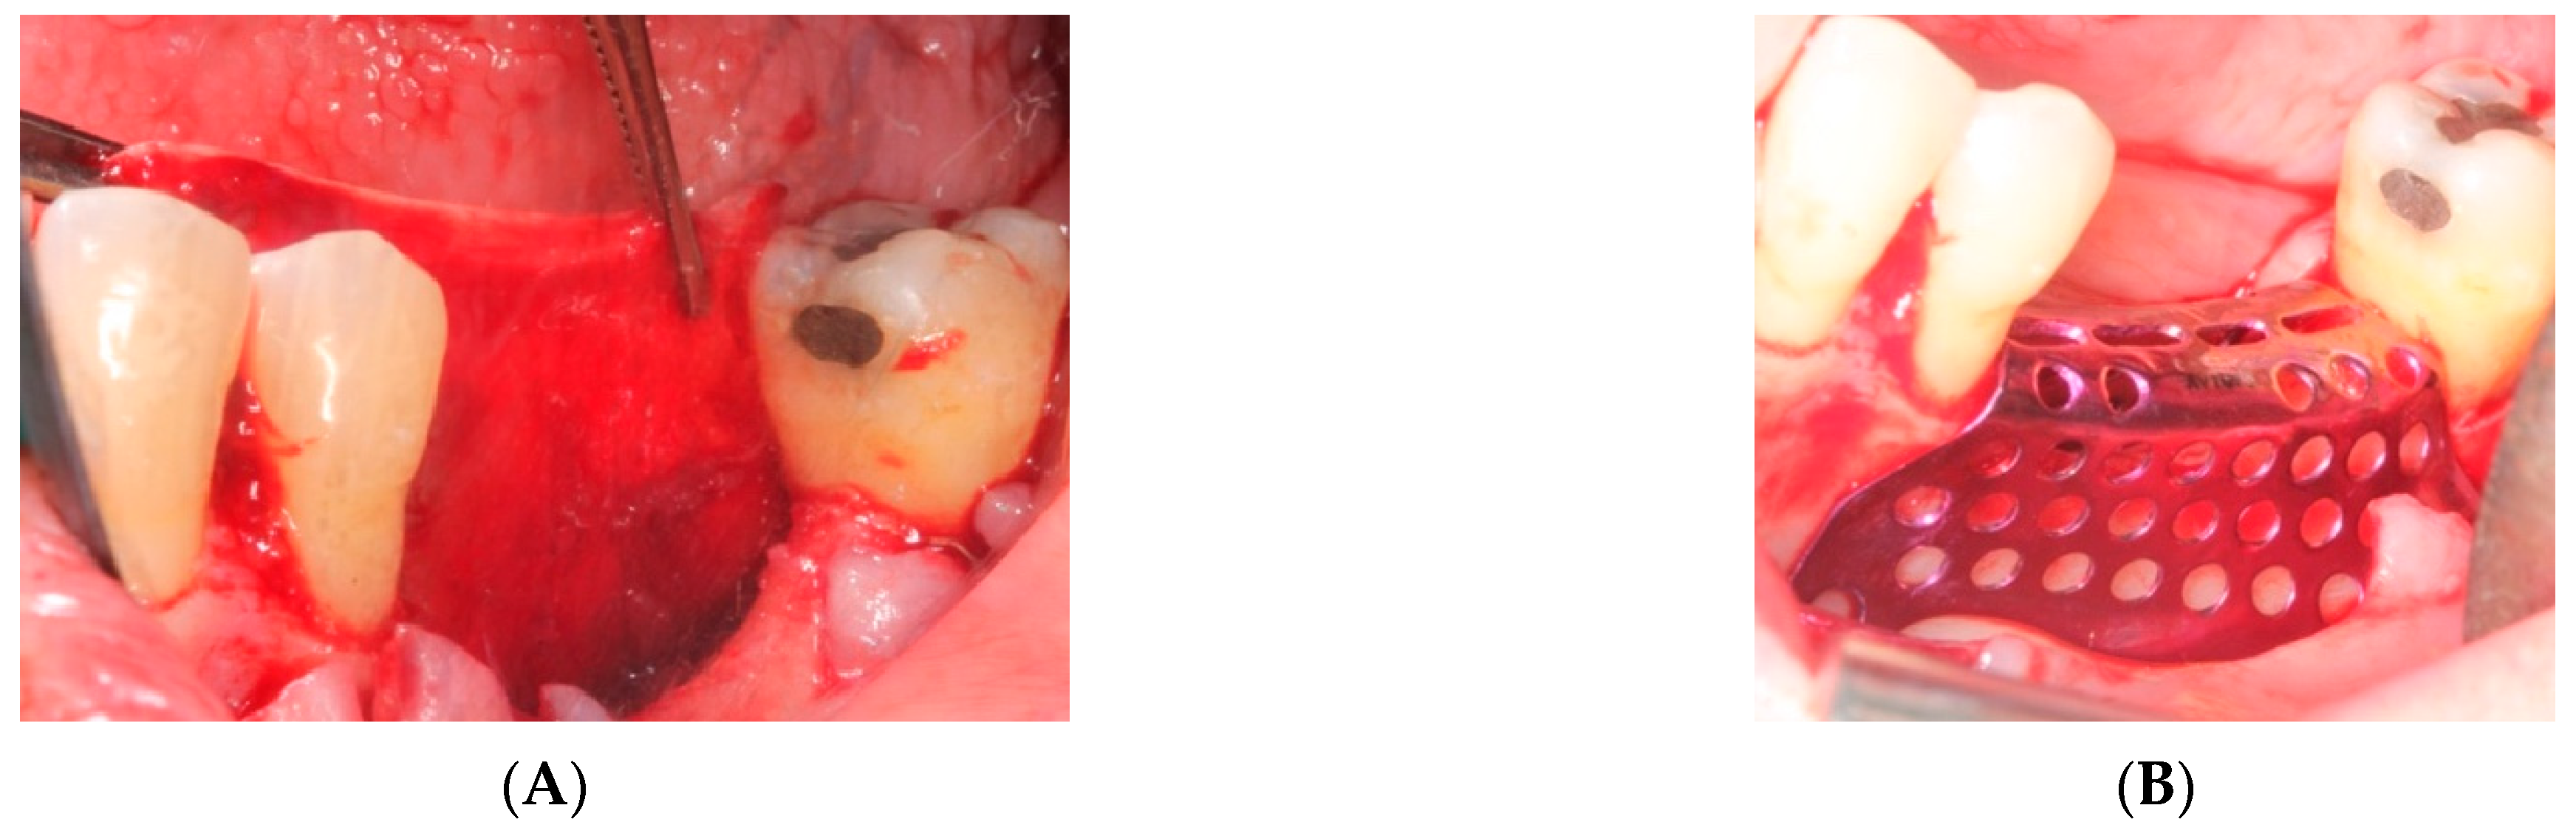

- First surgery: Local anesthesia Articaine 4% with epinephrine (1:100,000) was administered. An intrasulcular incision was made from the mesial of 3.3 to the distal of 3.7, continuing along the anterior border of the external ramus of the mandible. Periosteal incisions were made to mobilize the vestibular flap and the upper fibers of the mylohyoid muscle were disinserted to passivate the lingual flap and thus obtain a tension-free closure (Figure 3). We then checked the position of the mesh and proceeded to collect bone from the ascending branch using the bone scraper (Micross®, Selecdent, Barcelona, Spain) (Figure 4A). Cortical perforations were made to promote bleeding (Figure 4B). We mixed the autologous bone with the xenograft (Tioss®, Sanhigia, Bujaraloz, Spain) in a 70:30 ratio, inserted it into the mesh, and the mesh was placed in the defect.